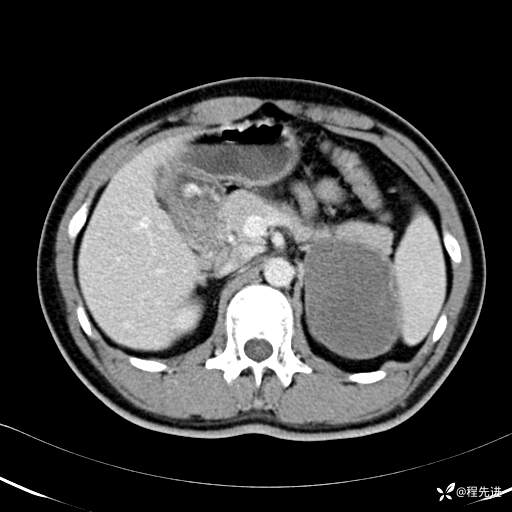

CT平扫:(CT值:平扫,27HU,动脉期,27HU,门静脉期,31HU,平衡期,32HU)